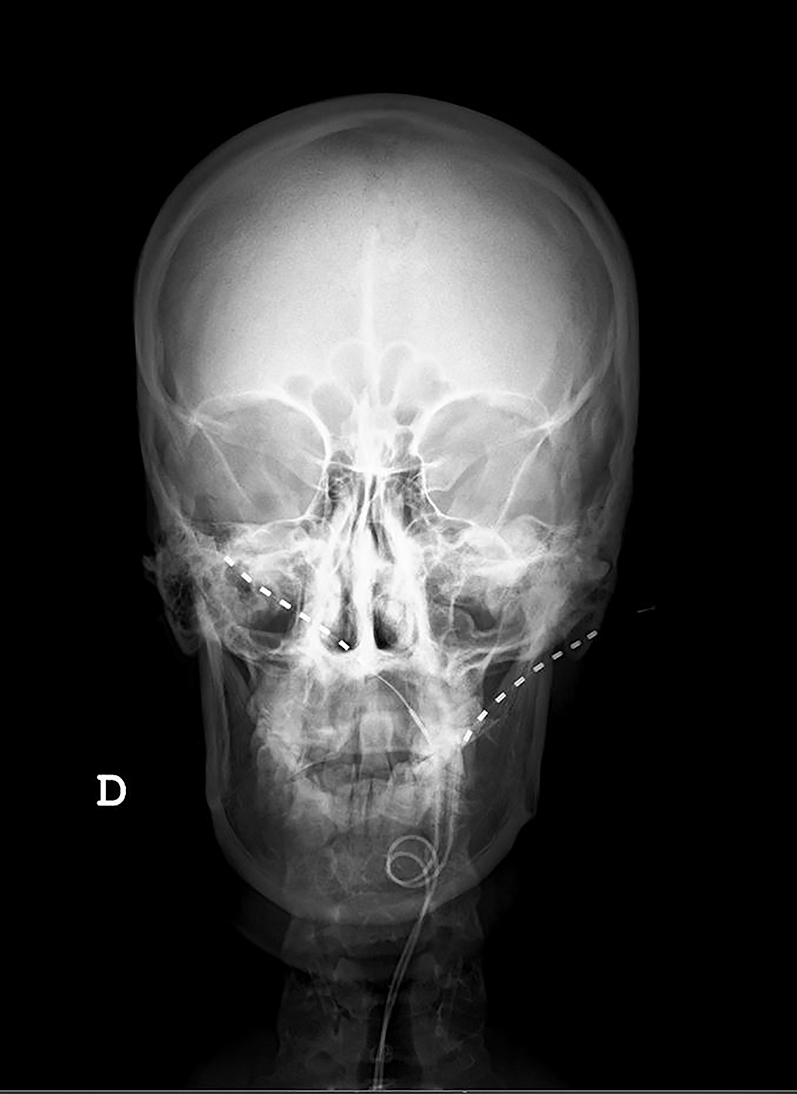

Twenty nine-year-old patient referred due to bilateral Arnold neuralgia and long-term cervicogenic headache. She was refractory to pharmacological treatment and repeated minimally invasive techniques on dorsal root ganglia and terminal branches of C2C3. According to previous background, the patient was scheduled for subcutaneous ONS. Under monitored sedation, bilateral occipital subcutaneous leads implant was performed. Two 90 cm Vectris Surescan electrodes, model 977A275 (Medtronic, Minneapolis, MN, USA), were placed with the introduction site at the level of C1C2. The tips of the leads in correspondence to the mastoid process were checked, the electrodes position overlapping with the patient’s pain area was monitored, without motor response to the cranial musculature that could lead to painful muscle stimulation [26] (in this phase the sedation was temporary interrupted to receive a functional feedback from the patient). Once adequate coverage was obtained of the symptomatic area, leads anchoring was done at the entry point , in the cervical paraspinal fascia using the Injex Bumpy lead anchor, model 97791 (Medtronic, Minneapolis, MN, USA). Strain-relieving, subcutaneous lead loops were used to absorb the stress of cervical movements, and minimize the risk of lead migration, as it is shown in Figures 1 and 2.

Radiographic scans at initial placement with leads entry point at C1 showing right higher than left placed.

Figures 1 and 2 show the final position of the implanted leads.